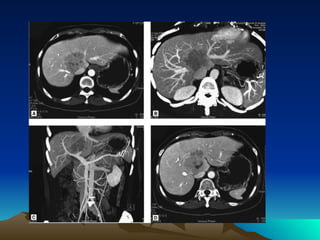

Ultrasound plays a significant role in screening and early detection of HCC , can detect 80% of tumors, tumors larger than 2cm can be found. It is a noninvasive examination and available for follow-up or screening, is a routine examination in chronic disease patient. CT&enhanced CT may find tumor less than 1cm ,enhanced CT aimed at diagnosing HCC take advantage of the hypervascularity of these tumors  and may differentiate from hepatic anginoma and other liver disease MRI  DSA  ECT  PET  Laparoscopy, percutaneous fine needle biopsy are also available. But the needle aspiration may add some hazard for hypervascular masses which can cause hemorrhage.

Computed tomography (CT) or magnetic resonance imaging (MRI) should be performed to better define the extent and number of primary lesions, vascular anatomy, vessel involvement, and extrahepatic disease. Helical CT or MRI should include early arterial phase enhancement.

Ultrasound plays asignificant role in screening and early detection of HCC , can detect 80% of tumors, tumors larger than 2cm can be found. It is a noninvasive examination and available for follow-up or screening, is a routine examination in chronic disease patient. CT&enhanced CT may find tumor less than 1cm ,enhanced CT aimed at diagnosing HCC take advantage of the hypervascularity of these tumors and may differentiate from hepatic anginoma and other liver disease MRI DSA ECT PET Laparoscopy, percutaneous fine needle biopsy are also available. But the needle aspiration may add some hazard for hypervascular masses which can cause hemorrhage.

Computed tomography (CT)or magnetic resonance imaging (MRI) should be performed to better define the extent and number of primary lesions, vascular anatomy, vessel involvement, and extrahepatic disease. Helical CT or MRI should include early arterial phase enhancement.